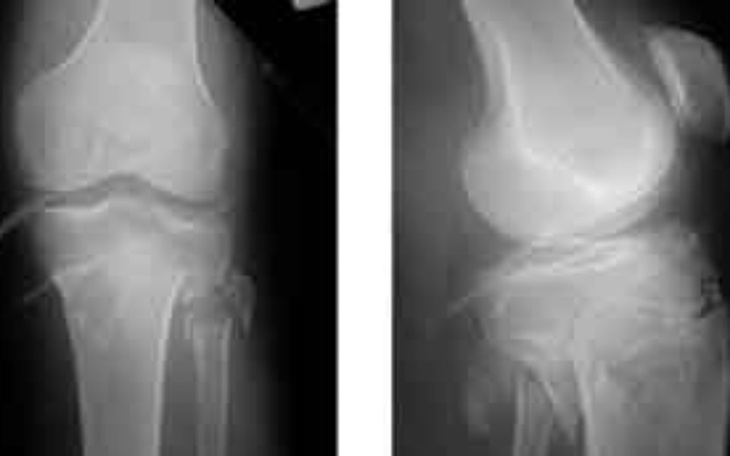

Wizyta kontrolna u ortopedy stwierdziła że po operacji mam skrzywienie kolana w osi ze stopą. Spowodowane jest to krzywo skręconą płytką oraz śrubami. W takim stanie nie wrócę do sprawności w najbliższej przyszłości. Mam problemy ze zginaniem kolana oraz stawu skokowego. Rozwiązaniem jest operacja w klinice prostującej Oś oraz usuniecie krzywo przykręconych elementów. Niestety ale nie ma możliwości zrobienia tego na NFZ ponieważ nie widzą problemu(sprawności kolana na 60% jest akceptowalne przez NFZ)i zostaje jedynie prywatna klinika plastyki kolana po której kolano wróci do zakresu 95% sprawności. Nie mogę wrocić do pracy ze względu na kolano a nie chcę być niepełnosprawny do końca życia z powodu ze system olewa ludzi w potrzebie.